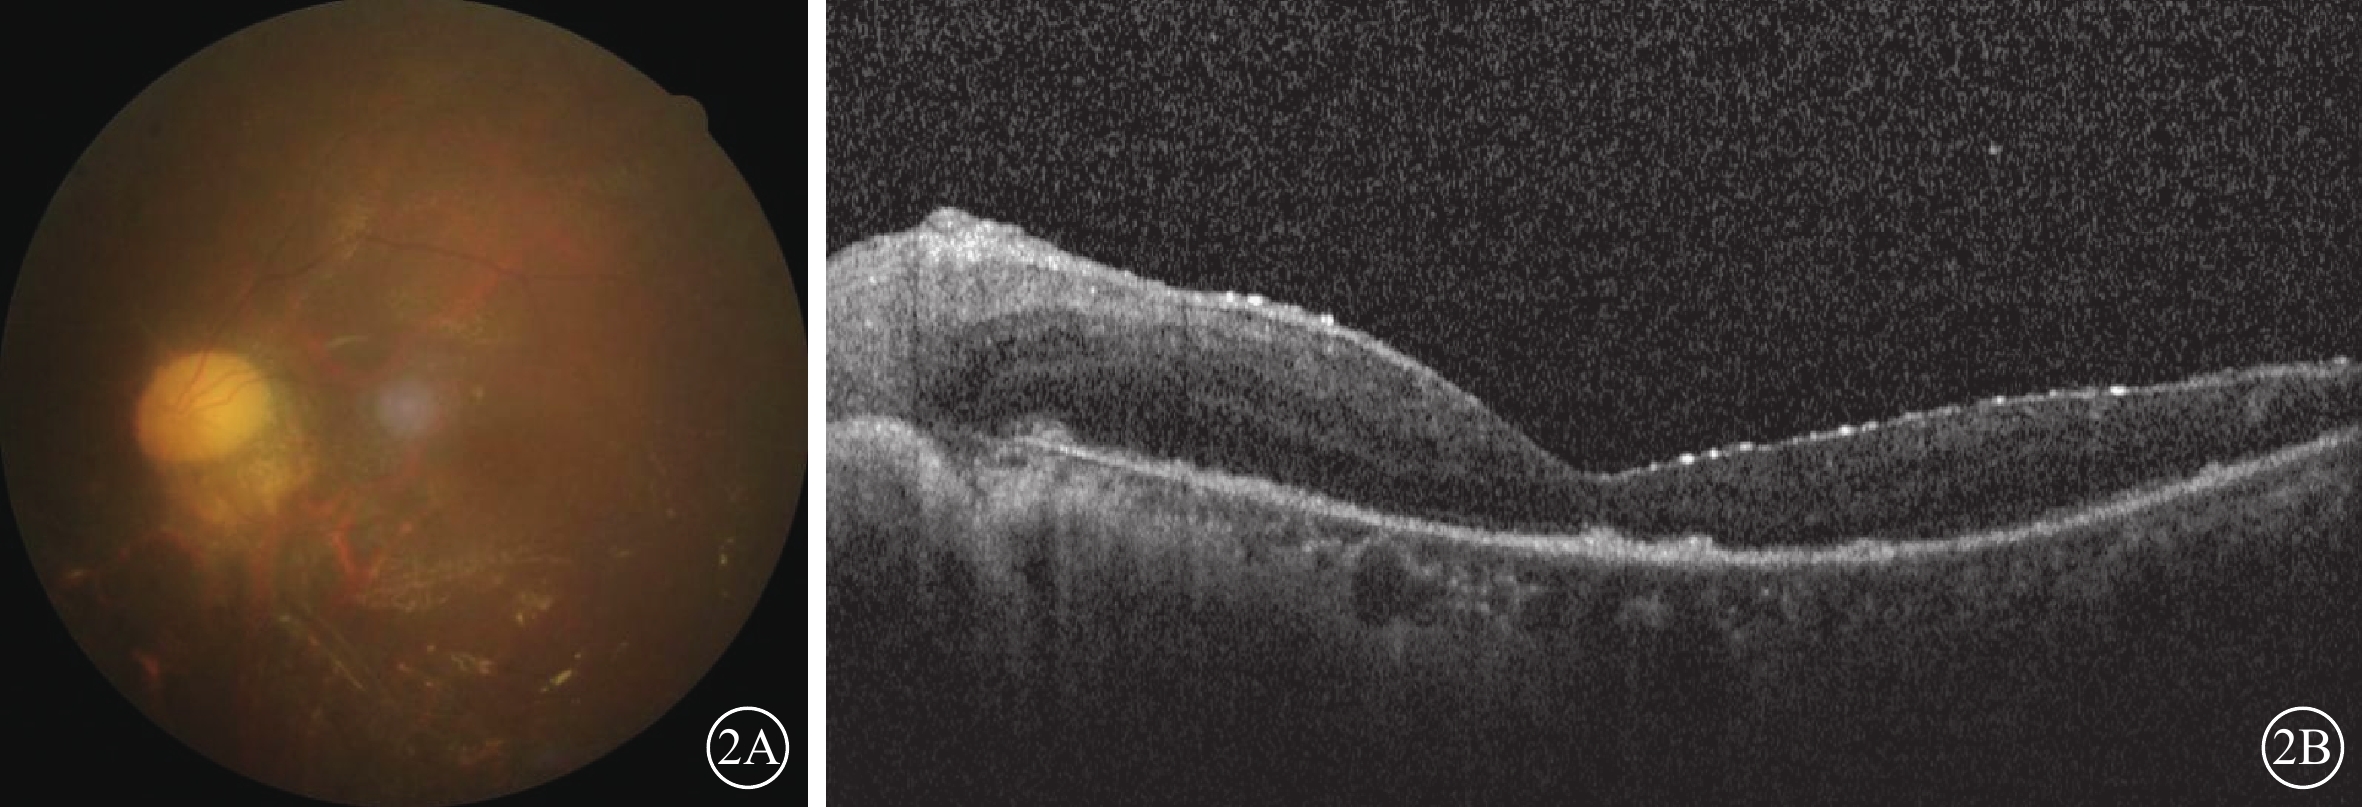

給予患者局部及系統抗病毒治療,玻璃體腔注射20 mg/ml更昔洛韋0.1 ml,每周2次,持續2周;每12小時靜脈滴注0.25 g注射用更昔洛韋,持續2周;口服泛昔洛韋分散片,0.25 g/次,3次/d,持續3個月。抗病毒治療后4 d開始,按1 mg/(kg·d)的劑量口服潑尼松龍,后逐漸減量。抗病毒治療后3 d,患者訴左眼眼球轉動痛緩解,但視力無改善。抗病毒治療后1周,眼底檢查可見左眼上方視網膜壞死灶。抗病毒治療后1個月,患者左眼因孔源性視網膜脫離行玻璃體切割聯合硅油填充手術。手術中見患眼視盤蒼白,黃斑區殘余小片灰白色水腫視網膜,伴血管白鞘;其余視網膜廣泛壞死呈“篩網”狀伴血管白線,可透見廣泛色素改變。手術后1個月,患者左眼視力眼前手動;眼底檢查可見左眼視盤蒼白,伴廣泛視網膜血管閉塞(圖2A);OCT檢查,左眼視網膜變薄、在位(圖2B)。